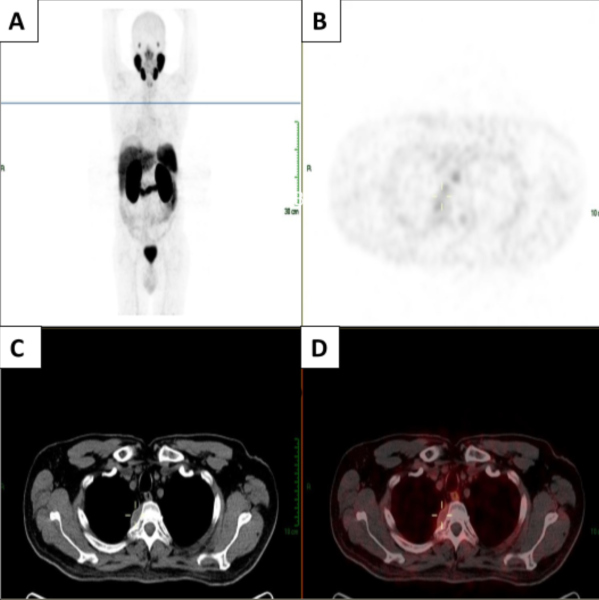

Se trata de un paciente masculino de 62 años con antecedente de adenocarcinoma de próstata Gleason 3+4 con recaída tumoral por elevación de PSA (0,88 ng/ml), por lo cual se solicitó PET/CT con 68Ga-PSMA. El estudio evidenció una masa con expresión de PSMA en el mediastino posterior, la cual fue resecada y el reporte de la patología fue un tumor derivado de la vaina nerviosa periférica (schwannoma). En el resto del rastreo realizado no se evidenciaron otras lesiones con expresión de PSMA. En el seguimiento, el paciente presenta aumento de los niveles de PSA (1,6 ng/ml) por lo que se decide realizar nuevo PET/CT con 68Ga-PSMA, el cual muestra la desaparición de la masa mediastinal descrita anteriormente, sin evidencia de otras lesiones. Se presentan las imágenes del PET/CT con 68Ga-PSMA inicial (Fig. 1) y el control posterior a la resección del tumor (Fig. 2).